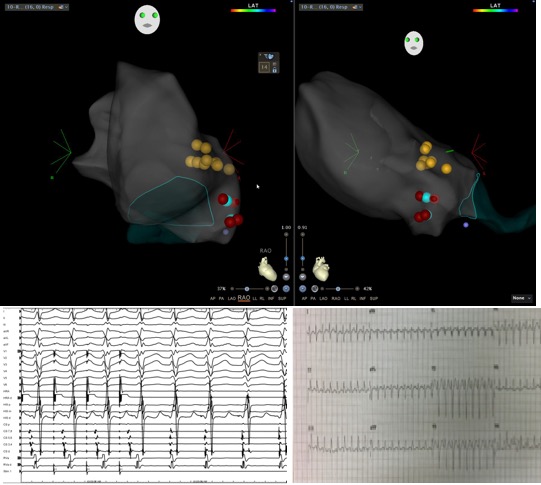

We hoped this would happen but did not expect it...termination of left atrial flutter during VOM ethanol infusion. Hopefully it helps this patient. Nice maps @ryancolemaps @maddyferraro1 @arcampado @MiguelVldrbno @TJHeartFellows

Nice example of propagation from a focal LAA-AT that also shows lateral to septal block across the anterior mitral line (and roof line too). Thanks @ryancolemap and your colorful EnSite X system and @MichaelCoMD (@TJHeartFellows) #EnsiteX